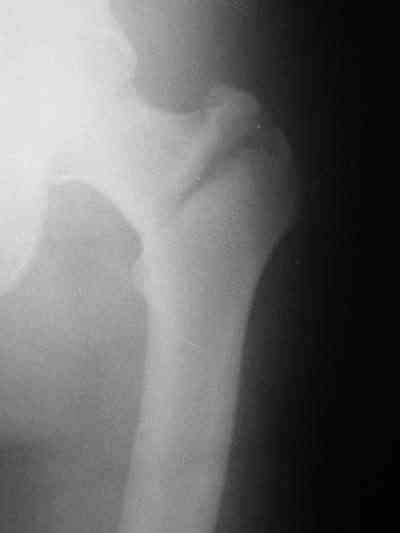

Снимки в приложении.

Конечно, при современном подходе, применение PFNa удленной версии со спиральным лезвием было бы адекватным решением. А также еще далеко до малоинвазивной техники, представленной А.Ю.Семенистым в издании Margo Anterior (МАТИС и AO/ASIF), где выполняется имплантация DHS через 4 сантиметровый разрез, снимаю шляпу перед этими мастерами, просто - высший класс, но ... какие наши годы!! ;-)

В приложении и имеющийся в наличии брейс. Приношу извинения за низкое качество снимков.